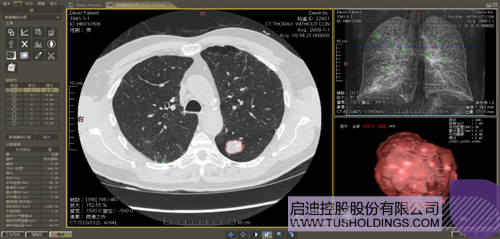

數字肺產品肺癌計算機輔助診斷

醫療影像智能分析是指運用人工智能技術、計算機視覺技術以及計算幾何技術對醫療影像進行自動分析,幫助醫生定位病癥、分析、跟蹤病情,并通過量化數據輔助醫生做出診斷,目前其旗艦產品“數字肺”已經覆蓋多種肺部疾病的早期檢測、診斷、跟蹤、術前規劃等完整的醫療流程。在臨床實踐中,超過80%的醫療數據來自醫療影像,這些影像數據通常需要專業醫生進行解讀,工作的重復性高、效率偏低。如果能夠運用智能影像分析技術,同時結合臨床表現以及既往病例進行全面分析,那么就可以大幅度提升影像診斷效率和準確性,讓專業醫生的寶貴時間集中在復雜病情的診斷和治療等環節。

數字肺——肺結節手術規劃系統